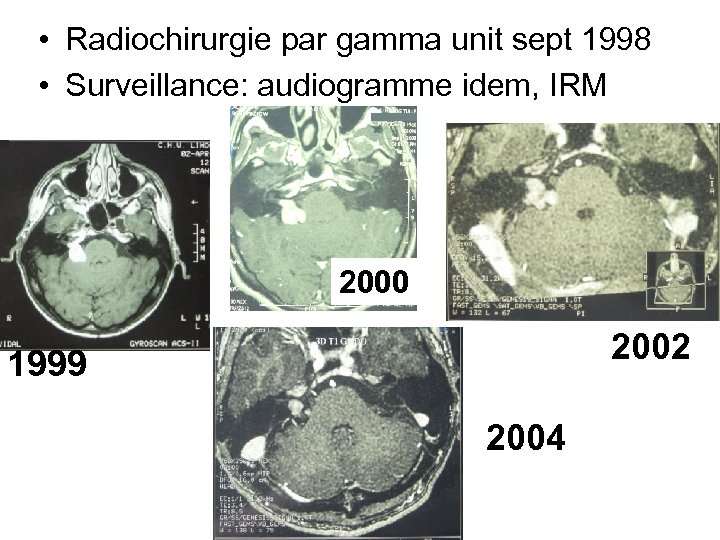

• Radiochirurgie par gamma unit sept 1998 • Surveillance: audiogramme idem, IRM 2000 2002 1999 2004

• Radiochirurgie par gamma unit sept 1998 • Surveillance: audiogramme idem, IRM 2000 2002 1999 2004